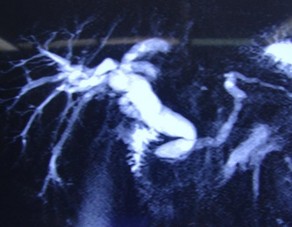

Bệnh nhân 1: Nguyễn Văn D, 1968 (50 tuổi) Mã bệnh án: 18-03-07934

Chẩn đoán: Ung thư biểu mô tuyến đầu tụy

Ảnh 1. Cộng hưởng từ trước mổ | Ảnh 2. Cắt ĐM vị tá tràng qua nội soi |